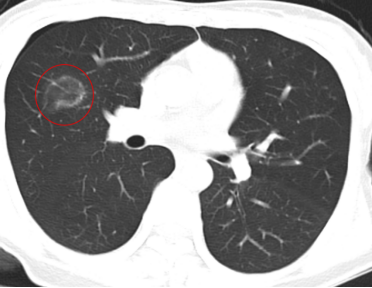

图中红圈内为该患者肺磨玻璃病灶

半个月前,她复查胸部CT发现肺内结节较前增大,进一步做了PET-CT检查,考虑原位或微浸润癌可能大。